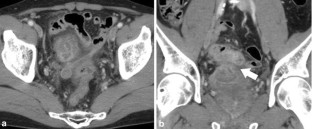

While there have been numerous reports about colovesical fistulas and ruptured intestinal diverticula, there have been far fewer reports about vesicointestinal fistulas caused by Meckel’s diverticula. Most Meckel’s diverticula are asymptomatic. Furthermore, they seldom cause vesicointestinal fistulas, and the associated complications are non-specific. Thus, their preoperative diagnosis is difficult. We experienced a case in which a vesicointestinal fistula was caused by a Meckel’s diverticulum and was treated with laparoscopic surgery. A 46-year-old male was referred to our hospital after exhibiting hematuria. Cystoscopy revealed a fistula between the small intestine and bladder. Contrast-enhanced computed tomography and magnetic resonance imaging showed a diverticulum in the ileum and a fistula between the ileum and bladder, which passed through the diverticulum. A Meckel’s diverticulum was suspected. We conducted a laparoscopic operation. We dissected the Meckel’s diverticulum with an automatic suturing device and removed it together with part of the ileum. The patient’s postoperative course was good. We experienced a case in which a vesicointestinal fistula was caused by a Meckel’s diverticulum and was successfully treated with laparoscopic surgery. In selected cases of Meckel’s diverticulum, the dissection of the diverticulum with an automatic suturing device is appropriate.

Fig. 2